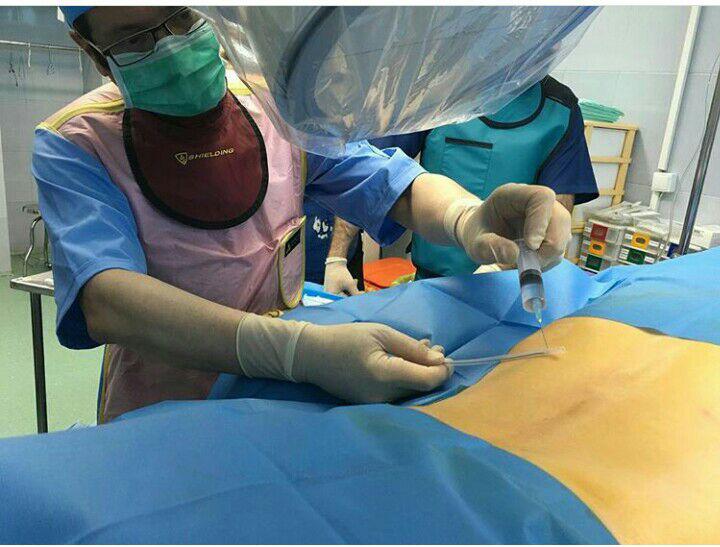

-PRP و اوزون تراپی آرتروز مفصلی

-اوزون تراپی دیسک بین مهره ای

استفاده از روشهایی مانند تزریقات تخصصی (مانند اپیدورال، بلوک عصبی)، طب سوزنی، فیزیوتراپی، تحریک الکتریکی عصب و روشهای کم تهاجمی جراحی.